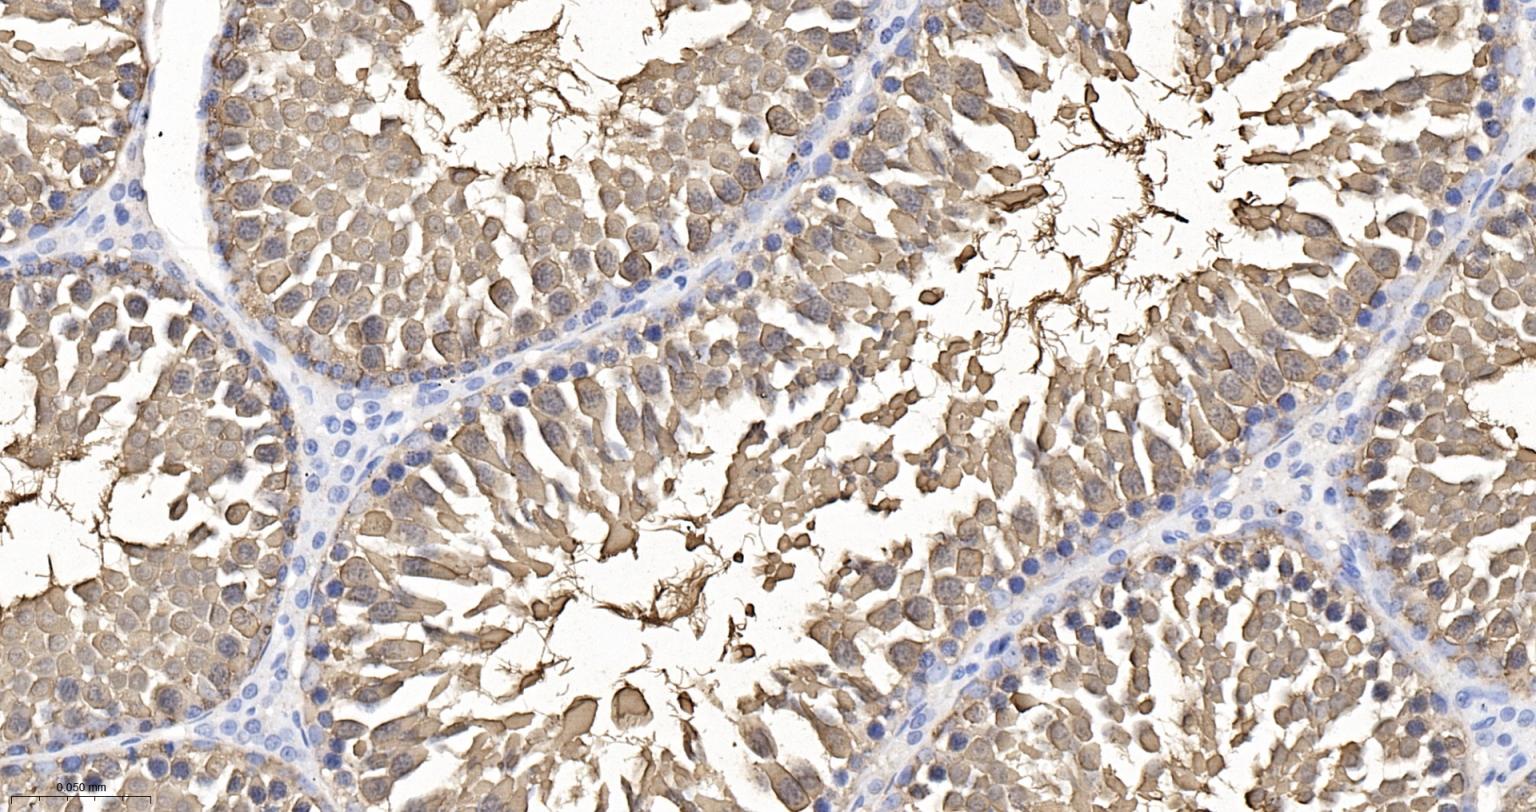

Paraformaldehyde-fixed, paraffin embedded Human Ovary; Antigen retrieval by boiling in sodium citrate buffer (pH6.0) for 15 min; The section was incubated with HSPA2 Monoclonal Antibody, Unconjugated (bsm-61353R) at 1:200 overnight at 4°C, followed by conjugation to the bs-0295G-HRP and DAB (C-0010) staining.

Paraformaldehyde-fixed, paraffin embedded Human Colon; Antigen retrieval by boiling in sodium citrate buffer (pH6.0) for 15 min; The section was incubated with HSPA2 Monoclonal Antibody, Unconjugated (bsm-61353R) at 1:200 overnight at 4°C, followed by conjugation to the bs-0295G-HRP and DAB (C-0010) staining.